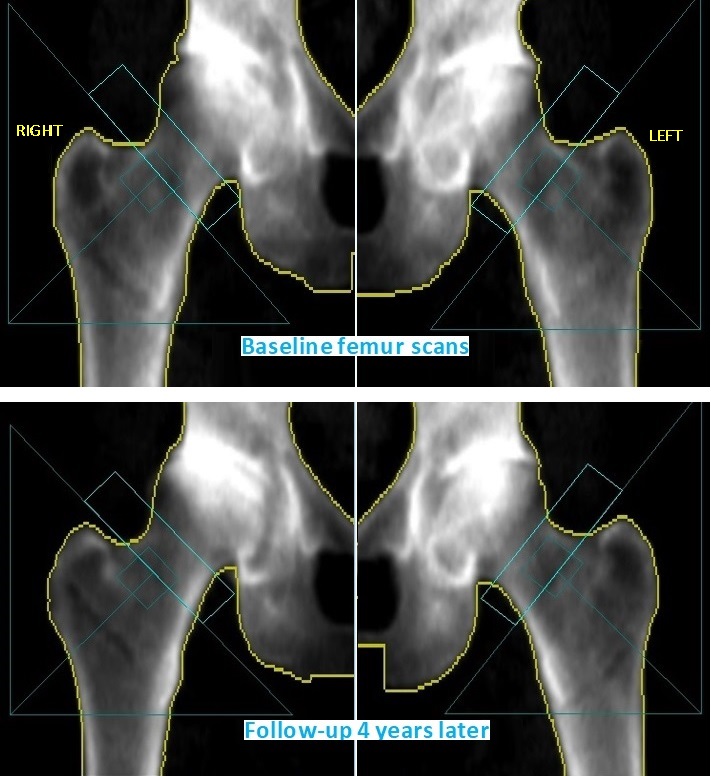

Discordant Left-Right Hip Change in Osteoarthritis

The left and right femoral neck BMD differ from one another significantly. Although there is no established cut-point for when this discordance should be considered unusual, this difference is nearly 2 standard deviations.

The right femur BMD is unreliable since it is based on abnormal anatomy resulting from osteoarthritis (OA). It should not be used for monitoring. Subsequently, the patient had right hip arthroplasty.

Between the baseline scan and follow-up, the right femoral neck BMD increased by more than 30% while the left neck remained stable. This same patient’s spine increased by 7% although it may have been somewhat falsely elevated due to sclerotic changes.

The patient stated that she is scheduled for a right hip replacement due to osteoarthritis. In OA, altered weight bearing stimulates abnormal bone formation at the inferomedial femoral neck. The cortex thickens in response to atypical mechanical stresses resulting in a “buttressing” effect (1). The morphology of one femur neck will differ from the other due to this adaptive phenomenon. Buttressing increases BMD measured at the neck. The unequal compressive load leads to local structural changes in femoral neck mineralization and resulting in physiologic discordance between the left and right sides especially related to weight bearing plays a key role (2).